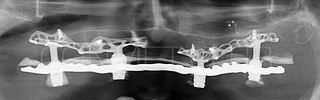

Результаты проведенных в 2017-2018 году операций субпериостальной имплантации показали их высокую эффективность, очень быструю адаптацию пациентов к новым зубам и отсутствие послеоперационного болевого синдрома. Интересной особенностью является труднодиагносцируемая, но точно присутствующая микроподвижность имплантатов спустя 6-12 месяцев. Учитывая данную особенность надо категорически избегать объединения субпериостальных имплантатов с естественными зубами или внутрикостными имплантатами!

Клинические работы с субпериостальными имплантатами производства Конмет, проведенные в 2019 году, позволили унифицировать интерфейс данных имплантатов под современный цифровой протокол. Более того, необходимые конструкционные элементы были введены в официальную базу под программу Exocad. Что позволило сократить время изготовления зубного протеза до 1-3 дней!